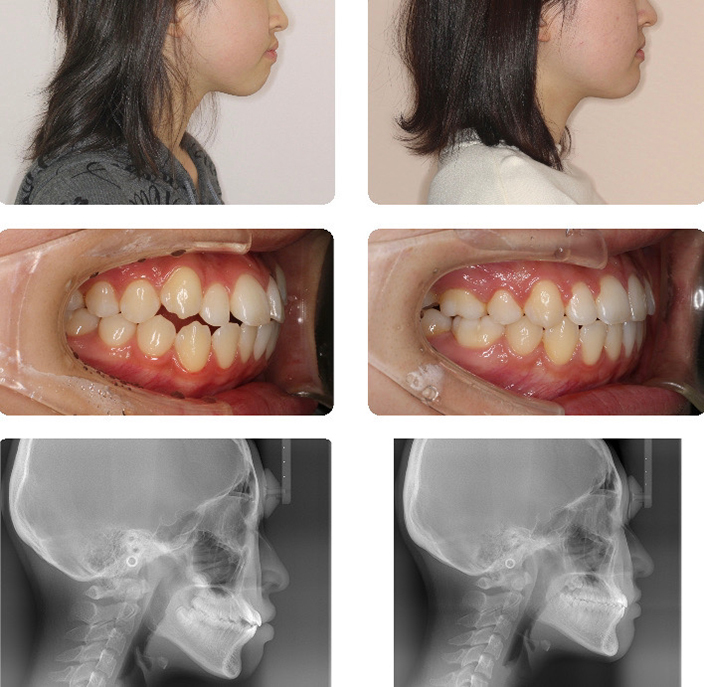

開咬

本症例は、1期治療で前歯が上下的に咬み合うことを目標に治療を進めました。

永久歯の交換に交換後、機能的咬合の確立のため2期治療に移行しました。

開咬(2期治療)

2期治療では歯列全体の整列と口元の審美的改善のため、小臼歯を抜歯しました。

上下顎前歯後退のために時間を要しましたが口唇閉鎖が容易となり、すっきり整った口元に改善が出来ました。